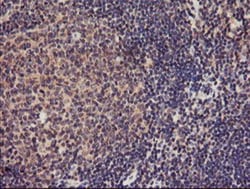

| Antigen | TMEFF2/Tomoregulin-2 |

| Applications | Western Blot, Immunohistochemistry, Immunohistochemistry (Paraffin) |

| Dilution | Western Blot 1:500-2000, Immunohistochemistry 1:150, Immunohistochemistry-Paraffin 1:150 |